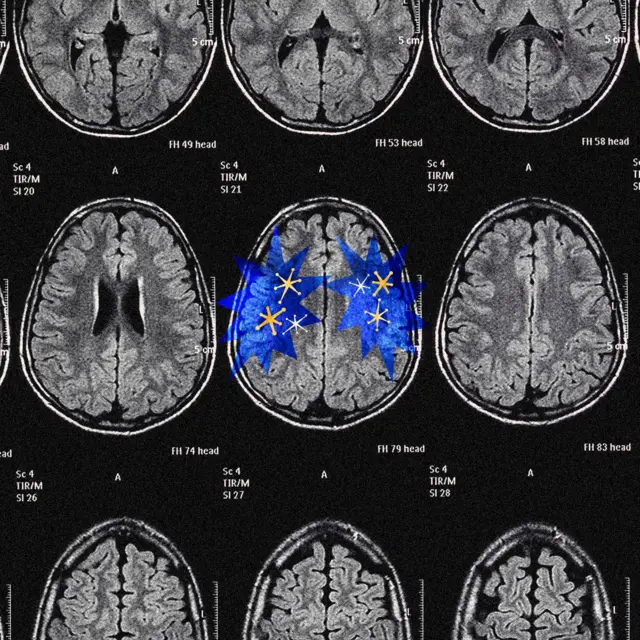

Щоб зрозуміти чому це так, нам потрібно подивитися, як дві частини нашого мозку - кора головного мозку і система винагороди, зокрема дофамін - штовхають нас у різні боки.

Автор фото, Serenity Strull